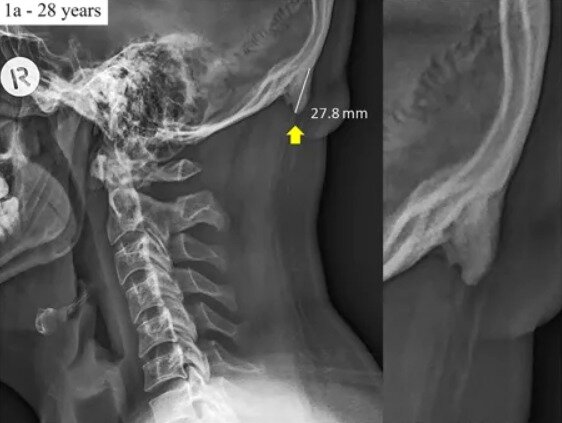

스마트폰이 두개골 구조 바꾼다…어떻게?

두개골 아래쪽 뼈 두툼해져…하중 버티려고 뼈 키워

본문 이미지 - 네이처닷컴 화면 갈무리ⓒ nature.com

네이처닷컴 화면 갈무리ⓒ nature.com